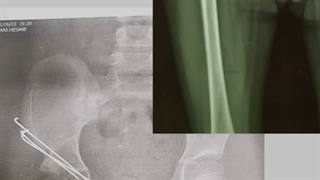

نتیجه درمان دررفتگی مادرزادی لگن بعد از هشت سال - برای اطلاعات بیشتر به آدرس سایت دکتر کاوه قرنی زاده متخصص ارتوپدی http://www.drgharanizadeh.com/ مراجعه کرده و یا با شماره های 09216682454 - 09390942494 تماس حاصل فرمائید.نشانی پستی :تهران – زعفرانیه -خیابان مقدس اردبیلی- نبش خیابان فرخ- ساختمان فرخ- پلاک ۱

نتیجه درمان دررفتگی مادرزادی لگن